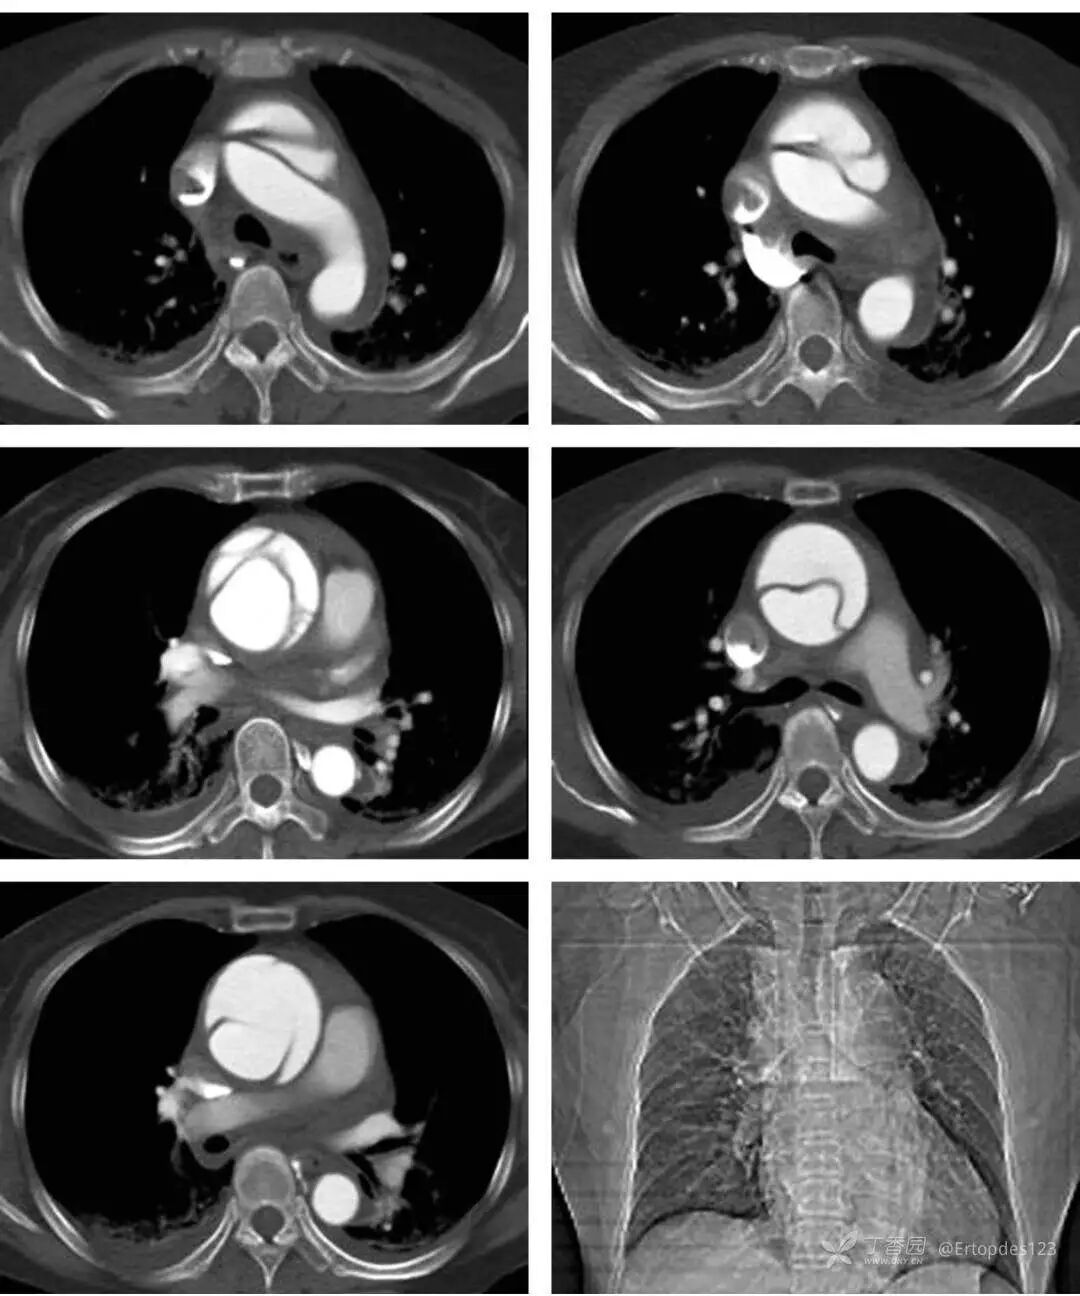

胸部CTA检查提示:升主动脉瘤样扩张,主动脉根窦部上方至主动脉弓平面管腔内均可见内膜片影,使其分成真假两腔,破口位于主动脉根部上方,大小约1.9cm。无名动脉、左颈总动脉及左锁骨下动脉未见受累,两下肺见条状高密影,边缘模糊,心包积液,双侧胸腔积液。(如图)

图片